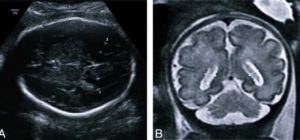

Показатели УЗИ, МРТ, проведенных до родов и после, в 57-83% случаев существенно отличаются. Если у плода обнаружили расширение желудочков, не стоит паниковать.

Для подтверждения или опровержения диагноза необходимо пройти повторное ультразвуковое и томографическое обследование новорожденного.

Первые симптомы вентрикуломегалии обнаруживают при помощи УЗИ, а уже на 20-33-й неделе беременности они становятся более заметными. Изредка патология фиксируется в начале 3 триместра, но диагностирование и определение симптомов лучше проводить на 25-26-й неделе.

Важно!Для постановки точного диагноза обязательно нужно провести несколько УЗИ в динамике, говорить о наличии патологии только по одному исследованию — невозможно.Диагностику заболевания рекомендуется проводить с 17-й по 33-ю неделю беременности. Для этого выполняют спектральное кариотипирование плода и делают УЗИ. Обязательным является проведение перинатальных обследований, при которых изучаются все анатомические структуры плода, и особое внимание уделяют системе желудочков.

Чтобы установить правильный диагноз, нужно выполнить поперечное сканирование головки плода — это позволяет определить пороговую величину боковых желудочков.